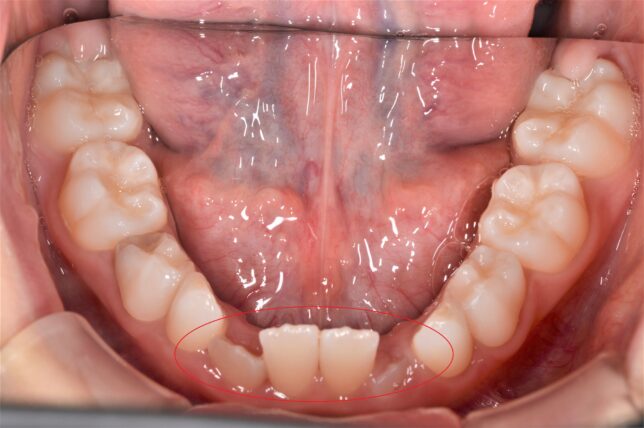

しかし、上下の永久歯の生えるタイミングだったり、遺伝的な顎の位置が原因で噛み合わせが反対(互い違い)になってしまうことがあります↓

永久歯の反対咬合は、自然に治りません。

治療後↓ 前歯の咬み合わせが、本来の咬み合わせになりました。

咬み合わせが治った直後ですので、前歯が隙間(すきっ歯)になっていますが、通常ですと、ほぼ自然に閉じていきます。